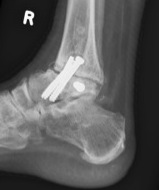

- neutral dorsiflexion, slight eversion / slight external rotation

- fix with 3 x 6.5 mm cannulated screws

- 2 medial and one lateral